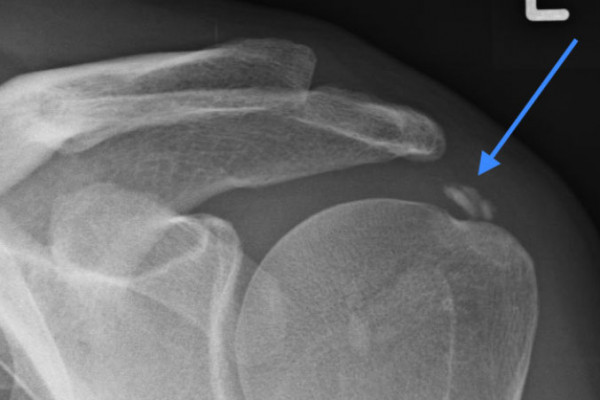

Kalkschulter Tendinosis Calcarea

Das Röntgen-Bild zeigt ein Kalkdepot in der Rotatorenmanschette der Schulter (Pfeil)